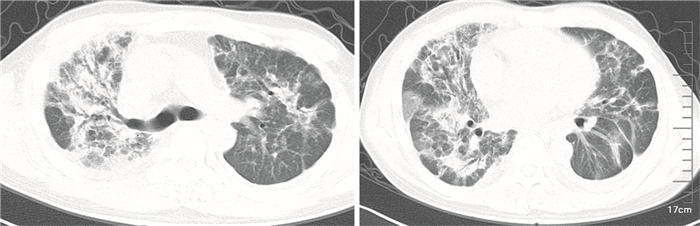

外院2014年4月26日胸部CT示雙肺廣泛性病變并縱隔淋巴結腫大,與2014年1月11日胸部CT平掃對比明顯改變(圖 1)。輔助檢查:白細胞12.2×109/L,中性粒細胞11.0×109/L;血氣分析:pH值7.415,二氧化碳分壓38.9 mm Hg,氧分壓71.7 mm Hg;腫瘤五項:神經元特異性烯醇化酶23.43 ng/mL,癌胚抗原7.32 ng/mL,糖類抗原125:71.27 U/mL,糖類抗原153:77.81 U/mL,非小細胞肺癌相關抗原5.03 ng/mL。心肌酶譜基本正常。炎性指標:降鈣素原正常,血沉正常。結核桿菌抗體測定、TB-DNA測定、真菌G試驗、念珠菌抗原檢測、巨細胞病毒定量、九項呼吸道感染病原體均正常。痰涂片及痰培養、氣管鏡涂片抗酸染色均陰性。免疫相關指標均正常。心臟彩超及腹部B超基本正常。肺功能因患者氣促嚴重無法執行。2014年4月29日胸部平掃+增強CT:(1)左肺腺癌;兩肺多發感染性病變,右側為著;(2)兩側胸腔少量積液,左側為著,左下肺壓迫性不張(圖 2)。2014年4月30日支氣管鏡肺活檢:(右上肺)送檢組織改變考慮為機化性肺炎(圖 3)。